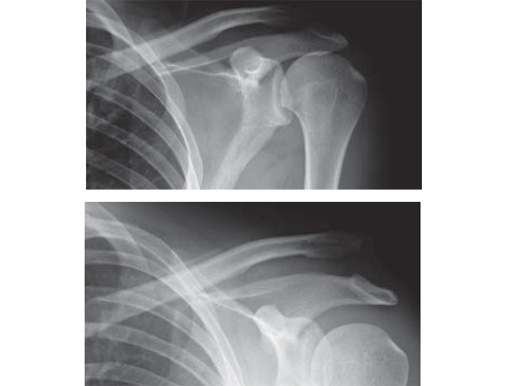

Fig.

Follow-up x-ray after 5 month. Stable AC joint, full function. Persisting ossification in coracoclavicular ligament without clinical relevance.Follow-up x-ray after 10 weeks. Begining ossification in coracoclavicular ligament.